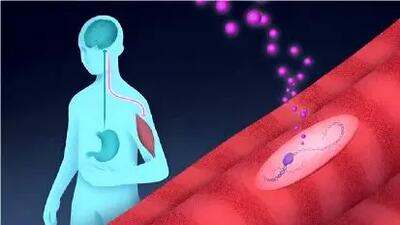

رگها را پس از سکته ترمیم می شوند

این ساختار سه بعدی مولکولهای درمانی را پس از سکته به مغز میرساند.